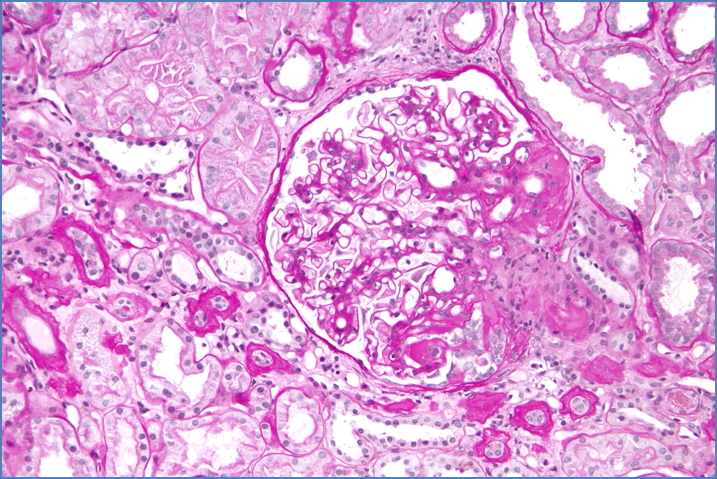

Nephron, CC BY-SA 3.0 <https://creativecommons.org/licenses/by-sa/3.0>, via Wikimedia Commons

- Segmental sclerosis in some glomeruli

- Hyalinosis on light microscopy